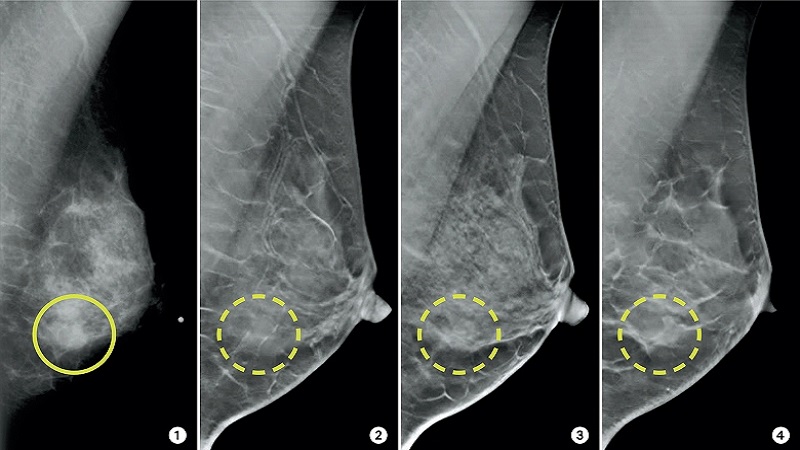

ماموگرافی در تصویربرداری دوبعدی سینه فشرده می شود، که گاهی اوقات باعث تجسم ظاهر مشکوک بافت کاملا سالم می شود: مثبت کاذب. مثبت کاذب با ماموگرافی 2 بعدی قابل توجه است، زیرا تخمین زده می شود که از هر دو بیمار یک نفر باید برای انجام معاینات تکمیلی عمیق تر، بدون نیاز، وقت ملاقات بگذارد. علاوه بر اضطرابی که چند برابر شدن این معاینات می تواند برای زنان ایجاد کند، نتایج مثبت کاذب هزینه های قابل توجهی را برای نظام سلامت به همراه دارد. این معاینه به طور کلی تشخیص سرطان سینه بیشتر را امکان پذیر می کند و در عین حال موارد مثبت کاذب را تا حدود 15 درصد محدود می کند.

انجام ماموگرافی سه بعدی

در مقایسه با ماموگرافی 2 بعدی، توموسنتز پستان دارای مزیت تولید تصاویر با کیفیت بالاتر است که امکان دید بهتر را برای رادیولوژیست فراهم می کند. نواحی تار یافت شده در دوبعدی، که گاهی نیاز به بررسیهای اضافی دارند، با این تکنیک جدید و دائماً در حال بهبود بیشتر قابل مشاهده میشوند. این افزایش دید با محدودیت برهم نهی بافت موجود در تصویربرداری دو بعدی توضیح داده می شود تا ساختار و خطوط سینه را بهتر تجسم کند.

علاوه بر این، ماموگرافی دوبعدی در تشخیص تومورها در بیماران جوان، که پستانهایشان اغلب متراکم است و امروزه تشخیص سرطان پستان در آنها هنوز مشکل است، مؤثر نیست.

ماموگرافی سه بعدی که با نام توموسنتز پستان یا ماموگرافی سه بعدی نیز شناخته می شود، یک معاینه تصویربرداری پزشکی است که قادر به بازسازی تصاویر پستان در مقاطع ظریف با استفاده از دستگاه مناسب است. با ماموگرافی سه بعدی، دستگاه در طول معاینه بر روی یک محور حرکت می کند تا تصاویر را از زوایای مختلف در کنار هم قرار دهد. این تکنیک تصویربرداری این مزیت را دارد که از برهم نهی تصویر که گاهی در ماموگرافی دوبعدی کلاسیک یافت می شود اجتناب می کند، زیرا این برهم نهی ها گاهی اوقات علت مثبت کاذب هستند.